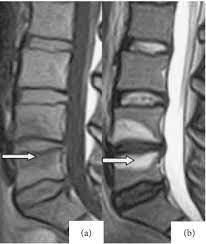

6. Disc herniation-

“The MRI confirms what we discussed in the first appointment - a bulge has likely happened slowly over time - the disc isn’t weak & vulnerable, and hasn’t just ‘slipped’ - it’s just got to point where it is causing mischief & irritating the nerve next to it” Image

7. “Most sciatic flare ups get better after 6 weeks. Don’t be afraid to keep moving- it’s safe! -take meds to help with this. If the pain doesn’t improve, the scan allows us to safely organise an injection to calm the nerve down”